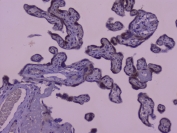

IHC staining of FFPE human placenta with Capicua antibody at 1ug/ml. HIER: boil tissue sections in pH6, 10mM citrate buffer, for 10-20 min followed by cooling at RT for 20 min.